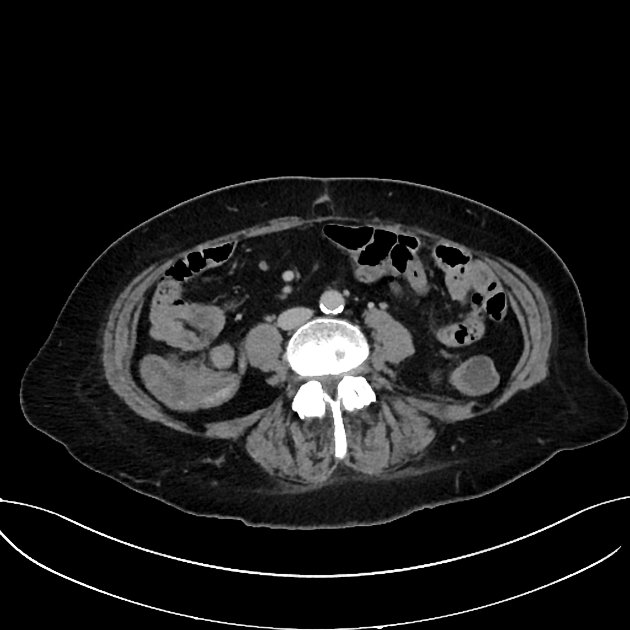

Axial C+delayed

Axial C+ arterial phase